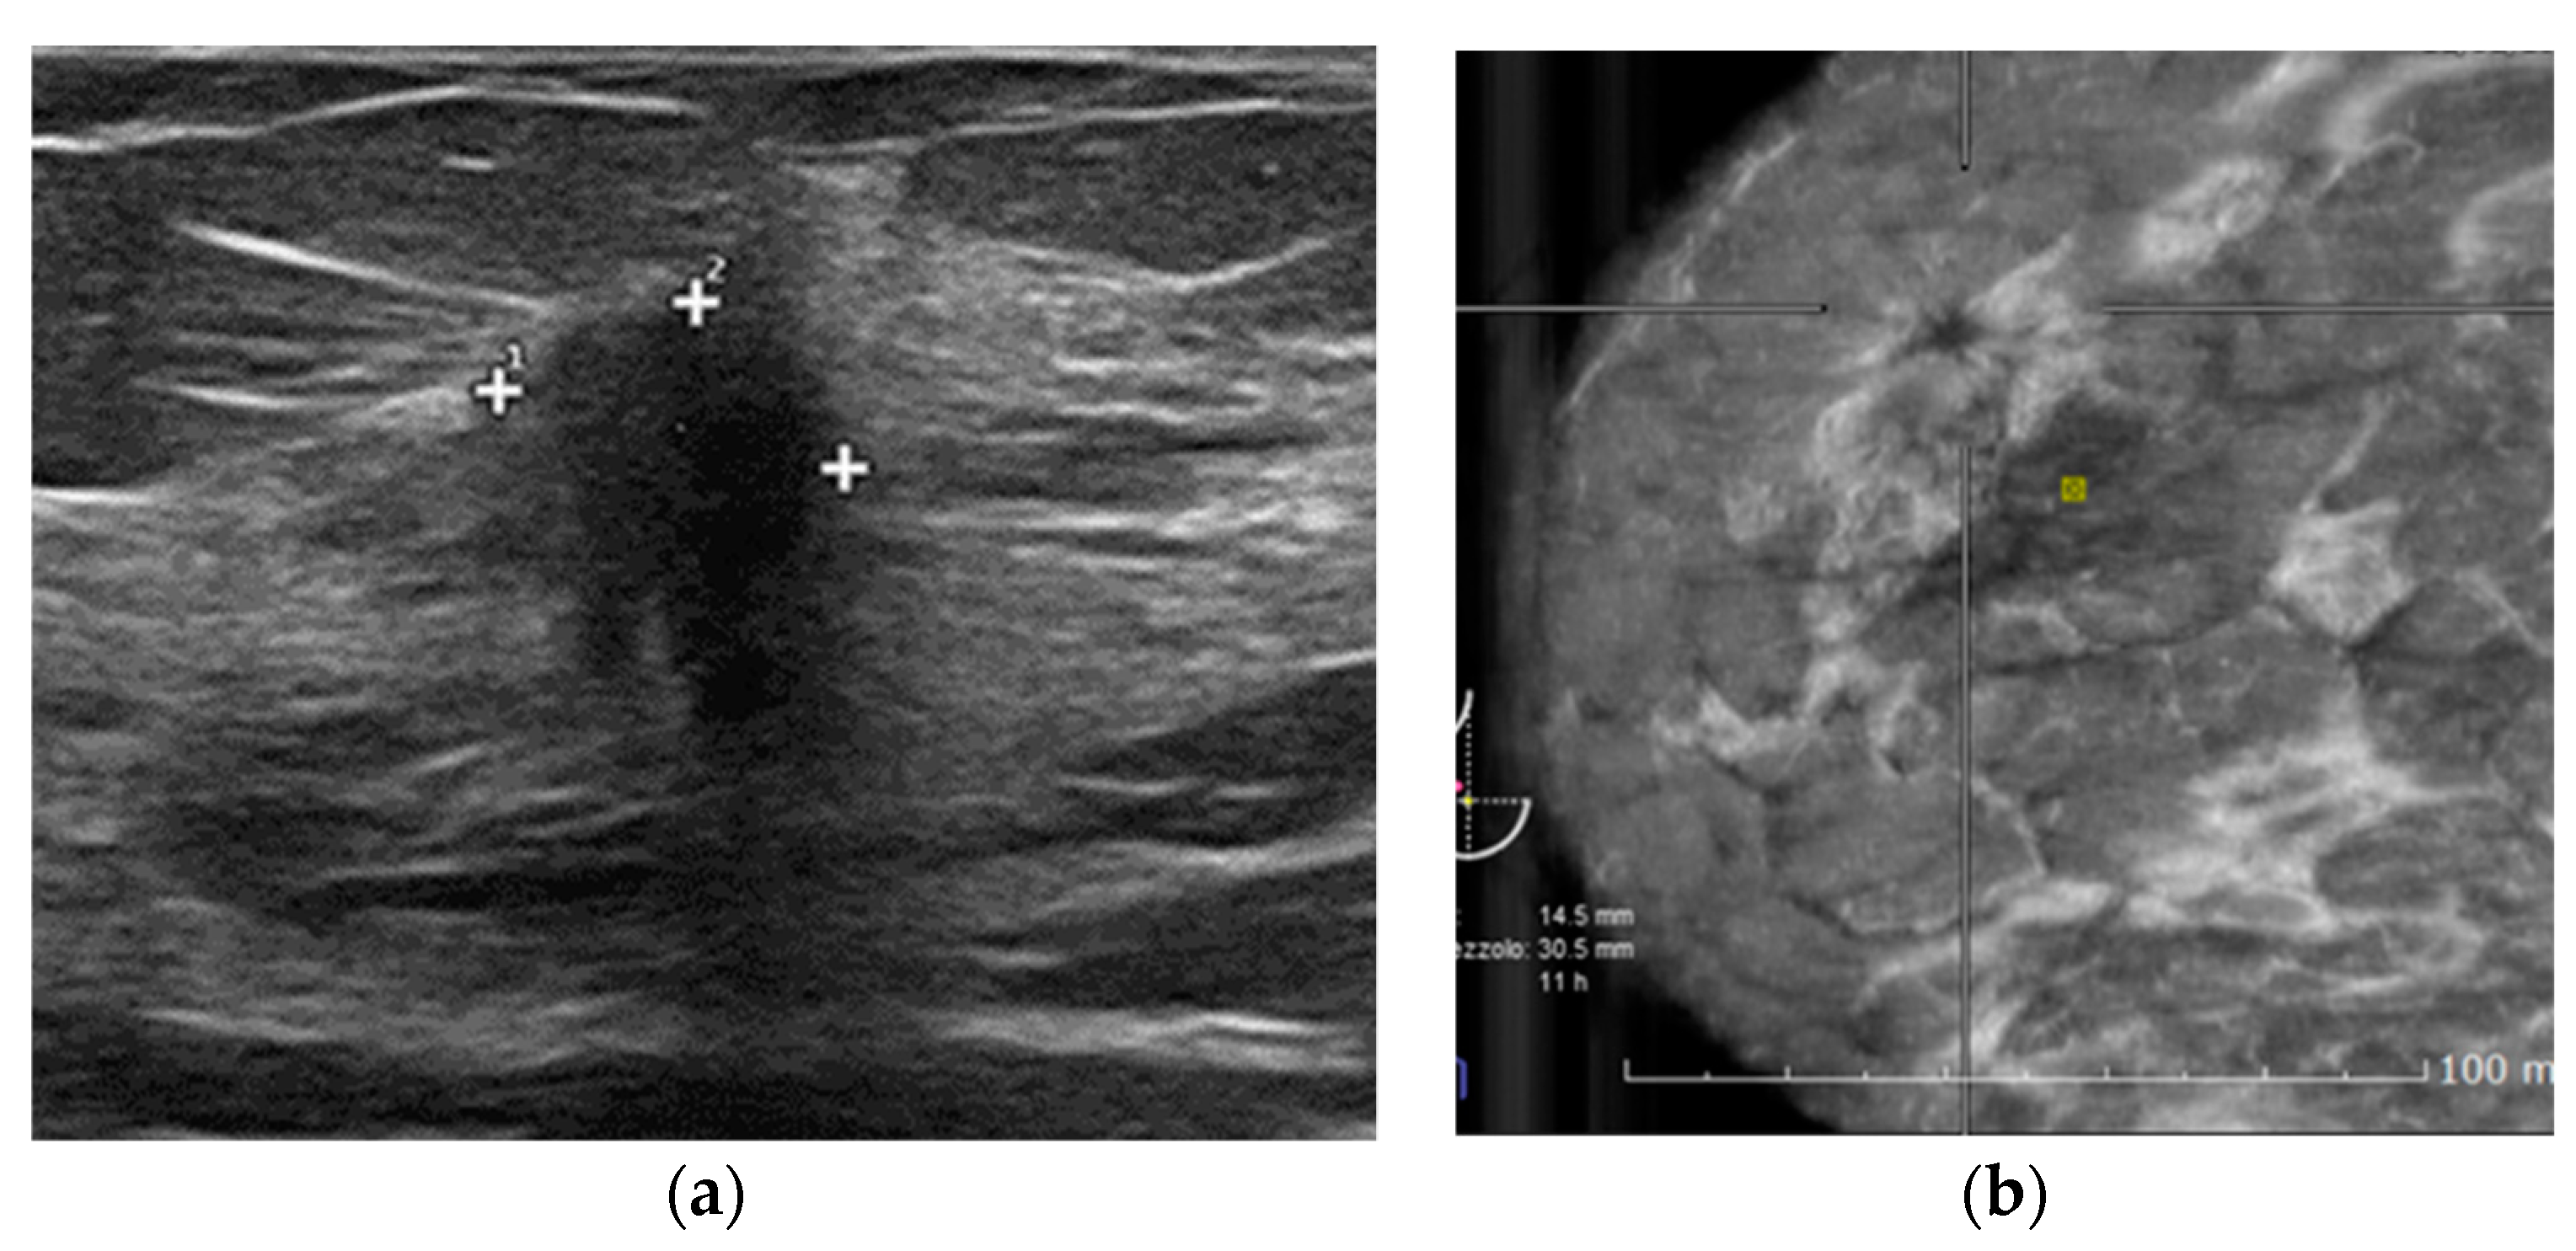

2.2. HHUS Examination

2.3. ABVS Execution

2.4. ABVS Interpretation

| Peripheral nodules | 5 |

| Small aggressive cancer | 2 |

| Retro areolar findings | 4 |

| Clinical findings | 2 |